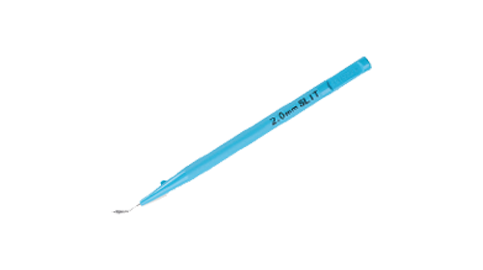

Eyebright Medical Technology (Beijing) Co., Ltd. (“Eyebright Medical”; SH Stock Code: 688050) is a National High-tech Enterprise and state-level technologically advanced "Little Giant" enterprises, located in Zhongguancun Science and Technology Park, Beijing, China. The Company is an innovation-driven ophthalmic medical device manufacturer. Its balanced product portfolio spans three major areas of the ophthalmic field: surgical treatment, myopia management, as well as consumer vision care. Anchored by its three core product categories - intraocular lenses, orthokeratology lenses, and soft contact lenses - the company has strategically expanded its product pipeline to cover the full life cycle of eye health solutions. Eyebright Medical is striding into a world-leading medical enterprise on behalf of China’s "Intelligent Manufacturing" power.